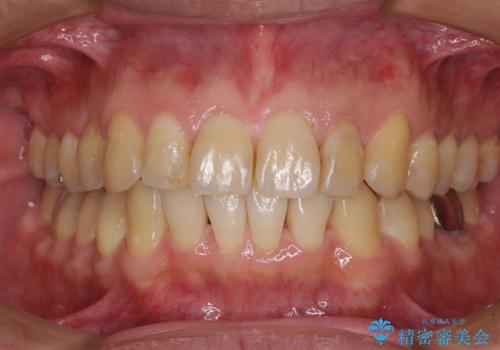

捻れて飛び出した前歯 インビザラインで整った前歯に

- 上下前歯のデコボコと、それに伴う出っ歯を気にして来院された患者様です。

インビザラインによる上下歯列の側方拡大と後方移動、IPR(歯と歯の間を削る)にるスペースの獲得により歯列を整えることとしました。

歯と歯の間を削ることでうまくスペースコントロールでき、また、毎日22時間以上しっかりとマウスピースを装着していただいたので、スムーズに治療が進みました。